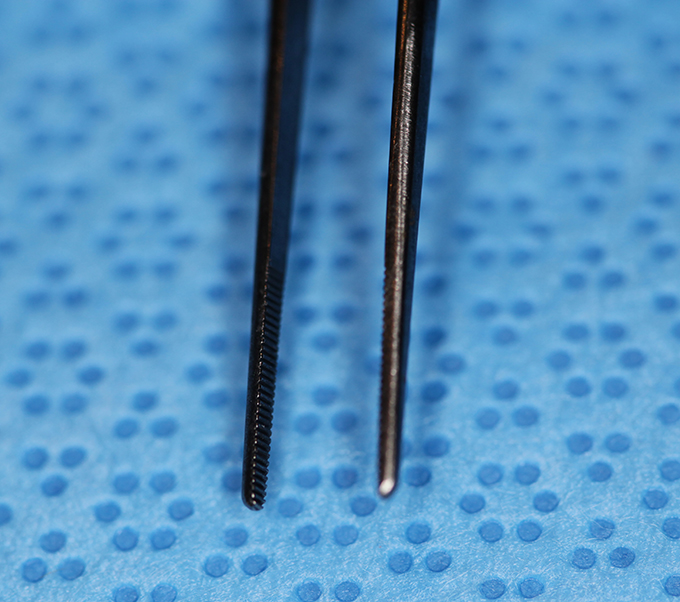

Forcep, Iris serrated straight 4" (Enlarged)

(aka smooth forceps)

catalog number: Storz E1400

Typical Use(s): Holding conjunctiva without teeth for glaucoma surgery